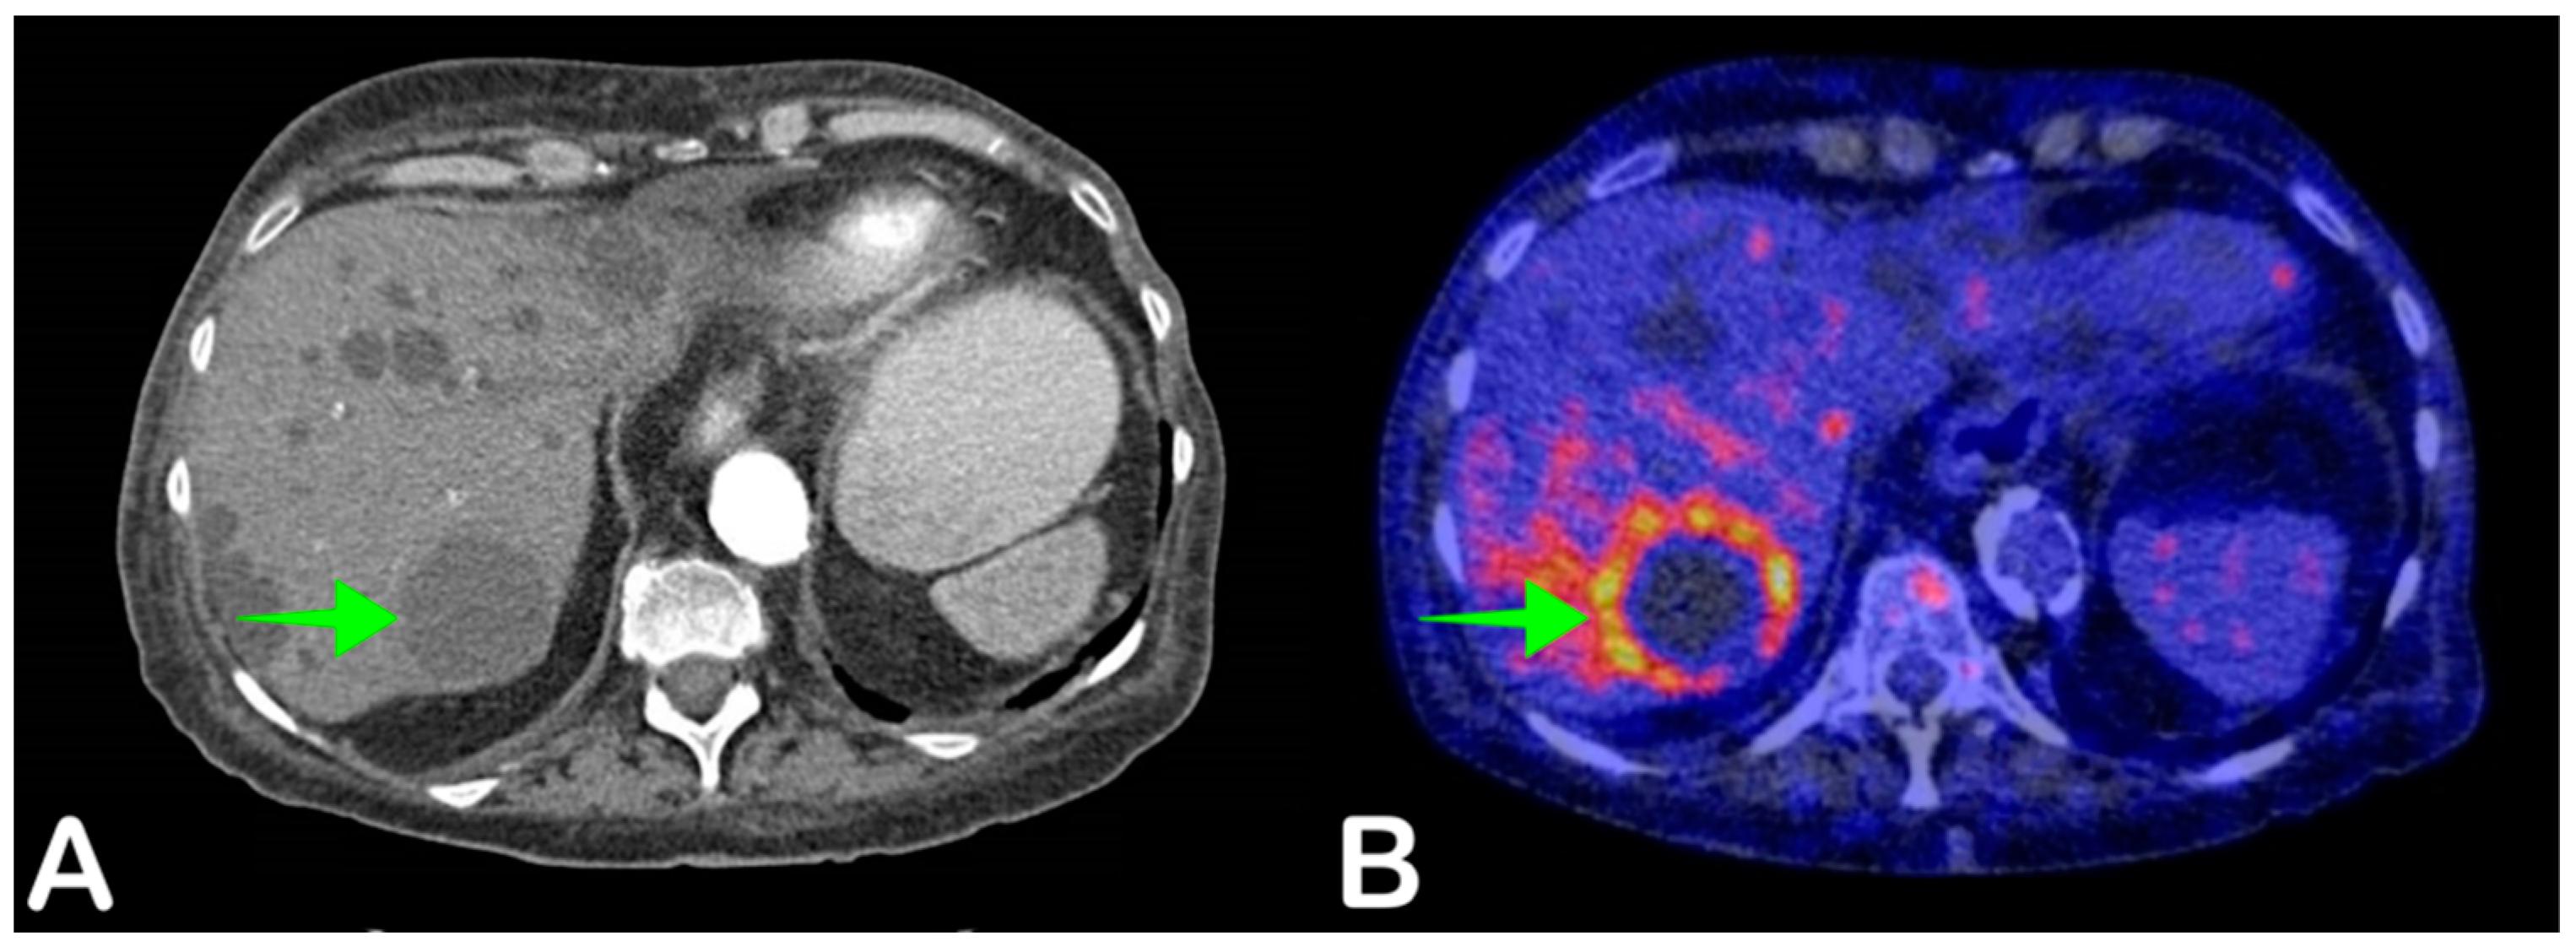

- Bobot, M.; Ghez, C.; Gondouin, B.; Sallée, M.; Fournier, P.; Burtey, S.; Legris, T.; Dussol, B.; Berland, Y.; Souteyrand, P.; et al. Diagnostic performance of [18F] fluorodeoxyglucose positron emission tomography–computed tomography in cyst infection in patients with autosomal dominant polycystic kidney disease. Clin. Microbiol. Infect. 2016, 22, 71–77. [Google Scholar] [CrossRef] [PubMed]

- Jouret, F.; Lhommel, R.; Beguin, C.; Devuyst, O.; Pirson, Y.; Hassoun, Z.; Kanaan, N. Positron-Emission Computed Tomography in Cyst Infection Diagnosis in Patients with Autosomal Dominant Polycystic Kidney Disease. Clin. J. Am. Soc. Nephrol. 2011, 6, 1644–1650. [Google Scholar] [CrossRef] [PubMed]

- Pijl, J.P.; Glaudemans, A.W.; Slart, R.H.; Kwee, T.C. 18F-FDG PET/CT in Autosomal Dominant Polycystic Kidney Disease Patients with Suspected Cyst Infection. J. Nucl. Med. 2018, 59, 1734–1741. [Google Scholar] [CrossRef]